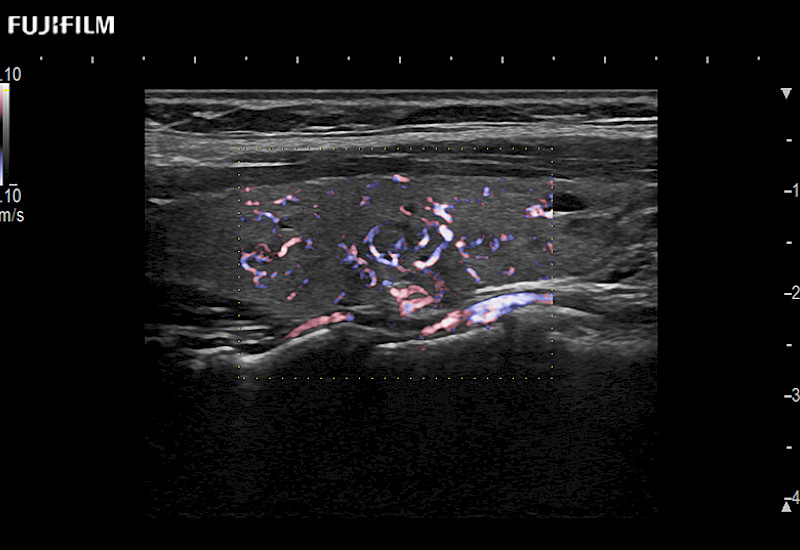

Our dedication to Surgical Oncology allows us to offer superior image quality, outstanding system reliability and intuitive use of cutting edge technology.